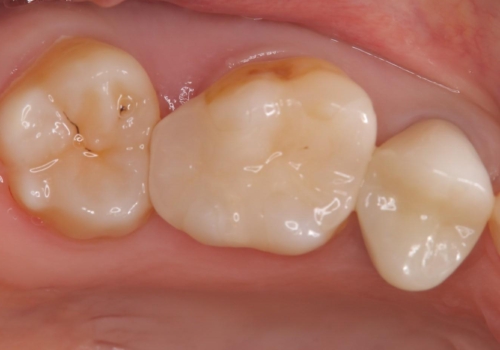

物が詰まりやすく歯茎が腫れる

- 元々入っていたセラミックインレーは、6番目と7番目の歯の隙間を無理やり咬合面の近遠心的幅径を伸ばし埋めたような形態で、下部鼓形空隙が広めで食渣が溜まりやすい状態でした。